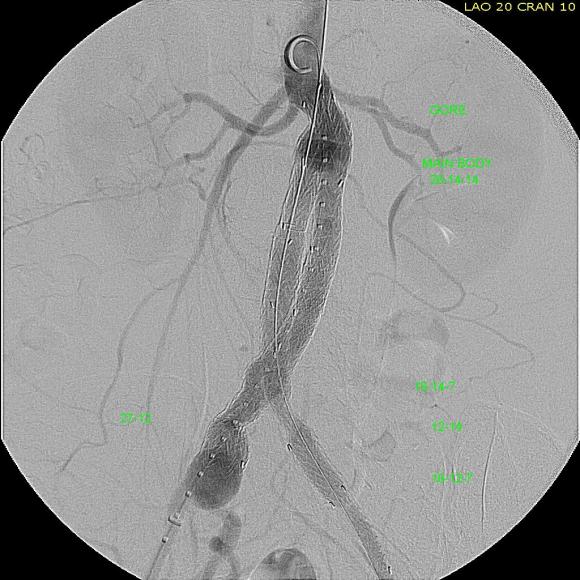

When faced with this kind of challenge, it makes sense and should be standard practice to get the opinion of the group. I happen to have excellent partners to run this kind of cases. The consensus was this: EVAR with accepting a short term result to temporize until definitive repair could be done. I found this acceptable. I chose to use the Excluder device because it allows for redos of the proximal deployment (C3 Delivery system) and the 23mm and 26mm devices used 16F access. A detailed discussion with the patient and the intention to eventually definitively repair open was discussed and patient was agreeable to proceeding. Plan B’s of Rifampin soaked graft replacement and NAS was also discussed.

I tried two things that was different. I felt that a stiff wire would result in horizontal orientation of the top of the graft, and so I placed a bend in the wire. Prior experience with unintended bends in wires have taught me that passing these wires is largely tolerated as long as it is done through catheters and sheaths. The other thing I did was bend the top of the delivery system -this was done with some care as I did not want to detach the contraining mechanism.

The wire and delivery system modification did tilt the top of the graft away from the left side of the aorta. It had the unintended effect of keeping the wall grabbing anchors away from the near wall while constrained.

It didn’t tilt the graft as much as I would have liked, but the graft deployed in a left to right fashion that allowed for controlled delivery across all of the available neck. Gratifyingly there was seal (below). I flared the right, while excluding the left iliac bifurcation because of the larger iliac aneurysm.